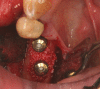

Peri-implant inflammations represent serious diseases after dental implant treatment, which affect both the surrounding hard and soft tissue. Due to prevalence rates up to 56%, peri-implantitis can lead to the loss of the implant without multilateral prevention and therapy concepts. Specific continuous check-ups with evaluation and elimination of risk factors (e.g. smoking, systemic diseases and periodontitis) are effective precautions. In addition to aspects of osseointegration, type and structure of the implant surface are of importance. For the treatment of peri-implant disease various conservative and surgical approaches are available. Mucositis and moderate forms of peri-implantitis can obviously be treated effectively using conservative methods. These include the utilization of different manual ablations, laser-supported systems as well as photodynamic therapy, which may be extended by local or systemic antibiotics. It is possible to regain osseointegration. In cases with advanced peri-implantitis surgical therapies are more effective than conservative approaches. Depending on the configuration of the defects, resective surgery can be carried out for elimination of peri-implant lesions, whereas regenerative therapies may be applicable for defect filling. The cumulative interceptive supportive therapy (CIST) protocol serves as guidance for the treatment of the peri-implantitis. The aim of this review is to provide an overview about current data and to give advices regarding diagnosis, prevention and treatment of peri-implant disease for practitioners.